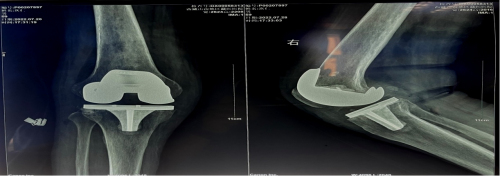

术后右下肢畸形明显矫正,假体位置安装精准

术中,根据截骨后骨缺损情况,选择使用了残留骨块按缺损大小填充植骨,予以使用2.4mm松弛骨螺钉加强固定,就不需使用昂贵的延长管及垫块等材料这样的手术技巧减轻患者经济压力同时又巧妙的保证了手术效果。术后患者根据个性化的康复锻炼方案,恢复良好。